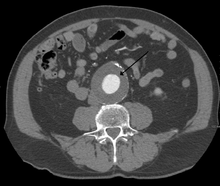

|

CT reconstruction image of an abdominal aortic aneurysm | |

The diagnosis of an abdominal aortic aneurysm can be confirmed at the bedside by the use of ultrasound. Rupture may be indicated by the presence of free fluid in the abdomen. A contrast-enhanced abdominal CT scan is the best test to diagnose an AAA and guide treatment options.